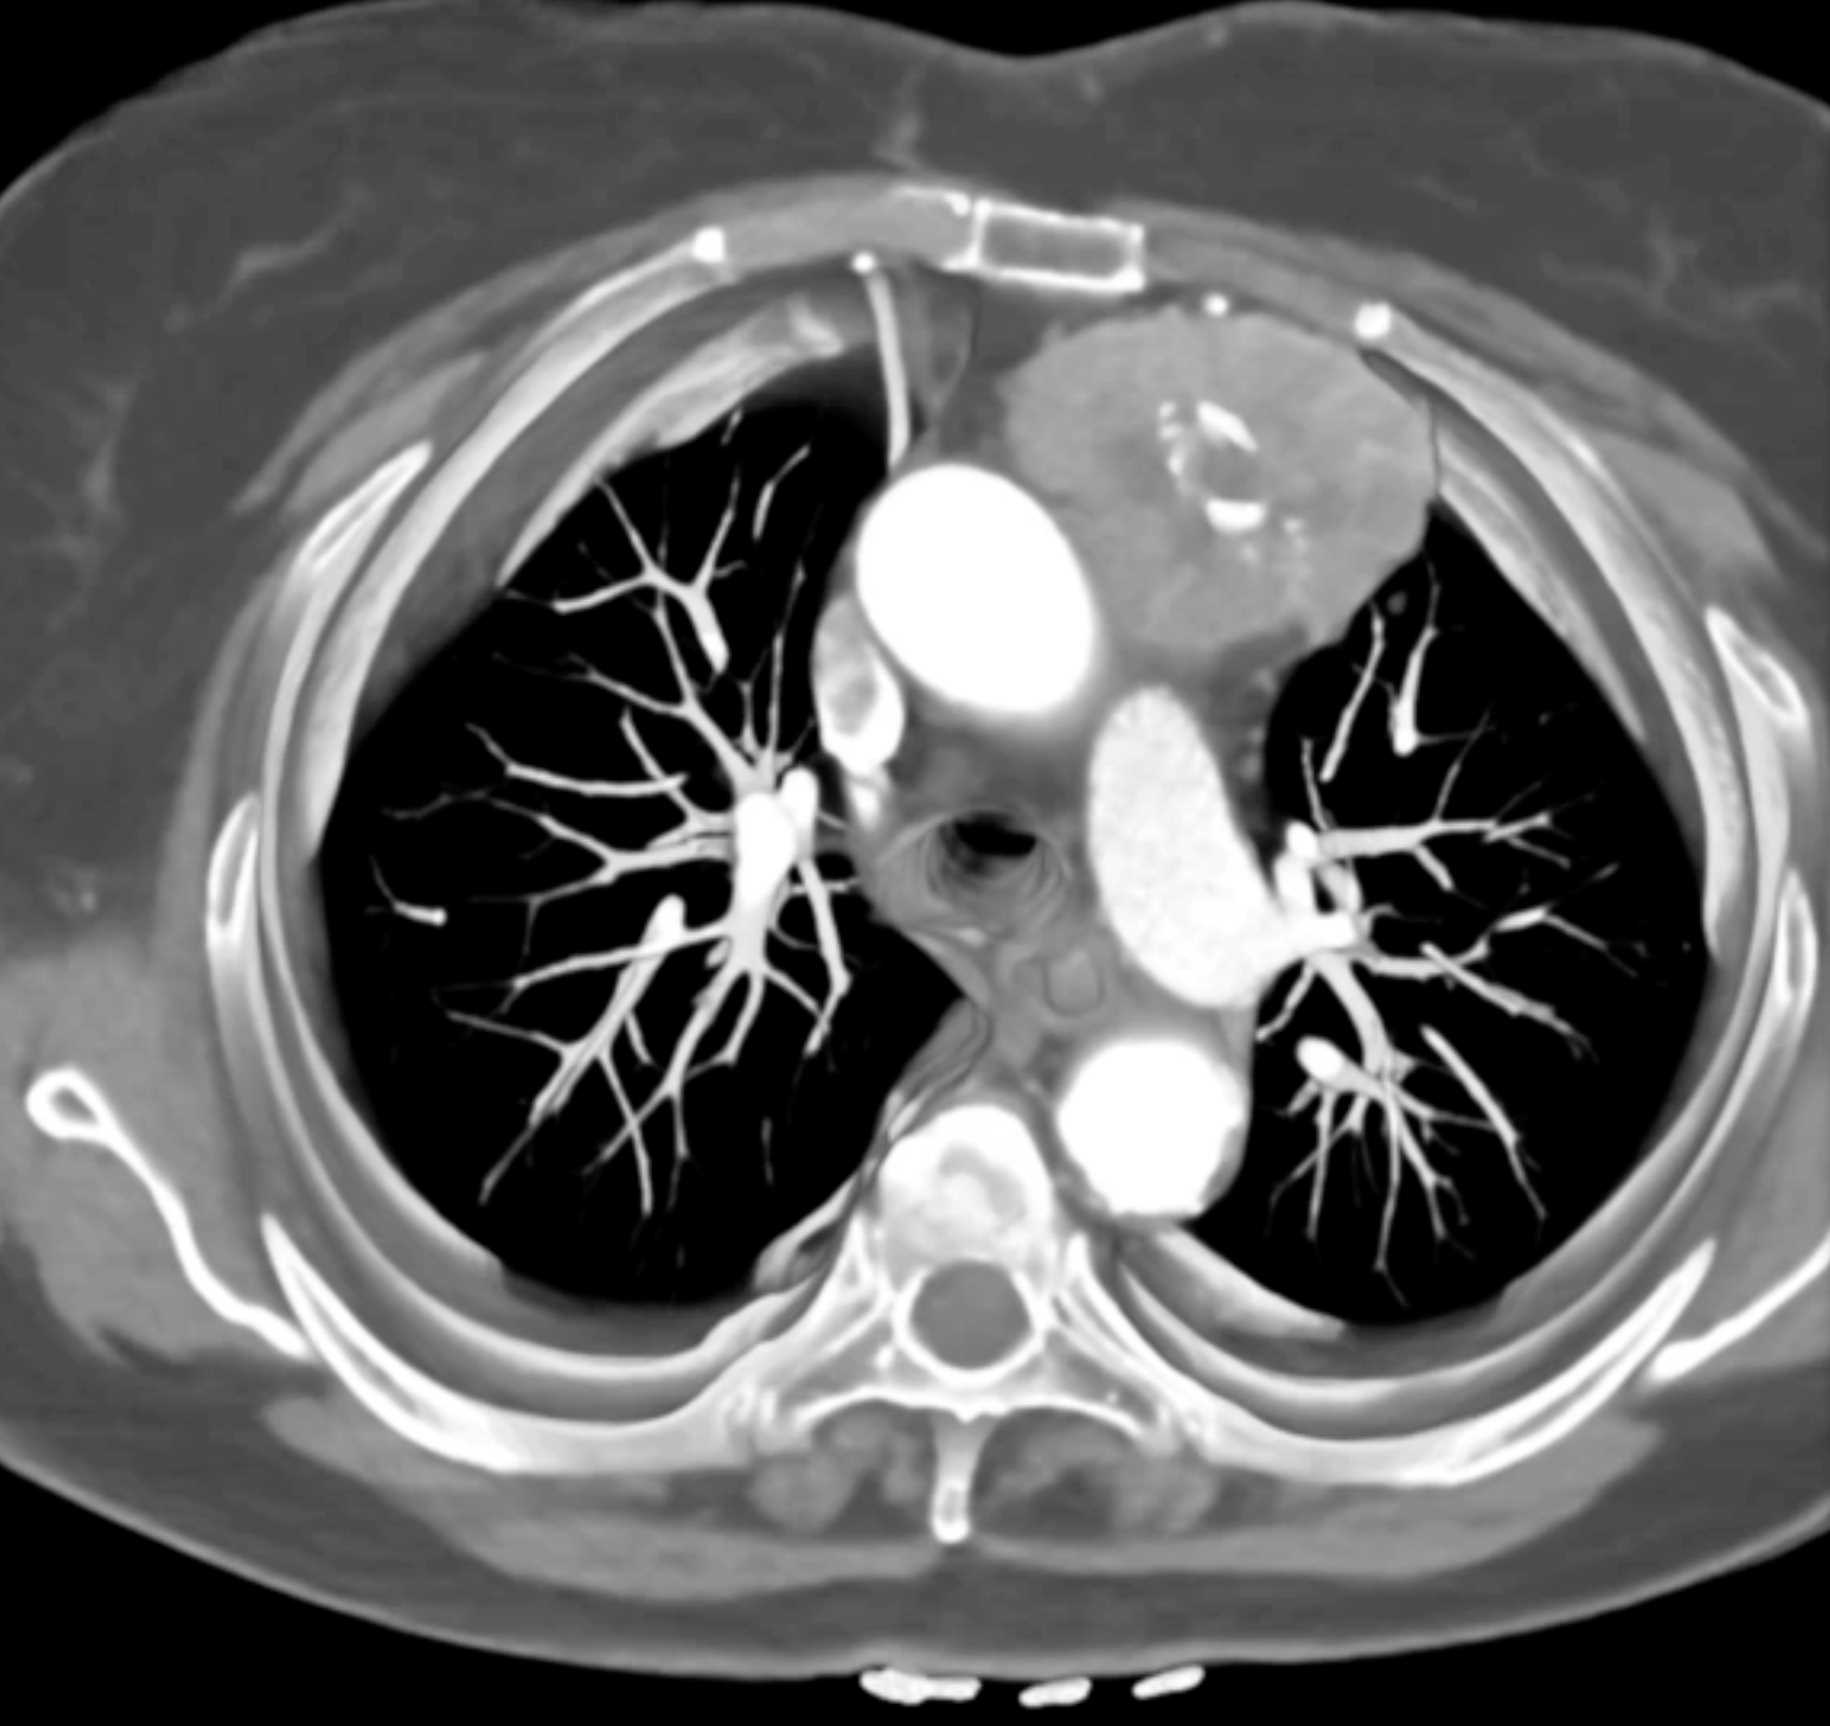

Thymic Carcinoma